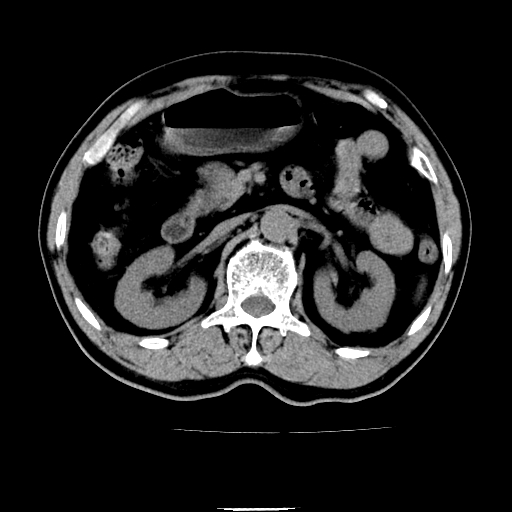

以下是引用chenqiong在2010-3-25 20:56:00的发言:[br]1、胆囊炎,胆囊息肉[br]2、肝内胆管及胆总管扩张,胆总管下端结石[br]3、十二指肠乳头旁憩室

以下是引用zxl51642在2010-3-26 10:47:00的发言:[br]胆囊炎,胆囊息肉,胆总管扩张,但未看到明显肿块,肝内胆管扩张不像恶性,炎性狭窄或阴性结石可能吧,建议mrcp,右肾小囊肿